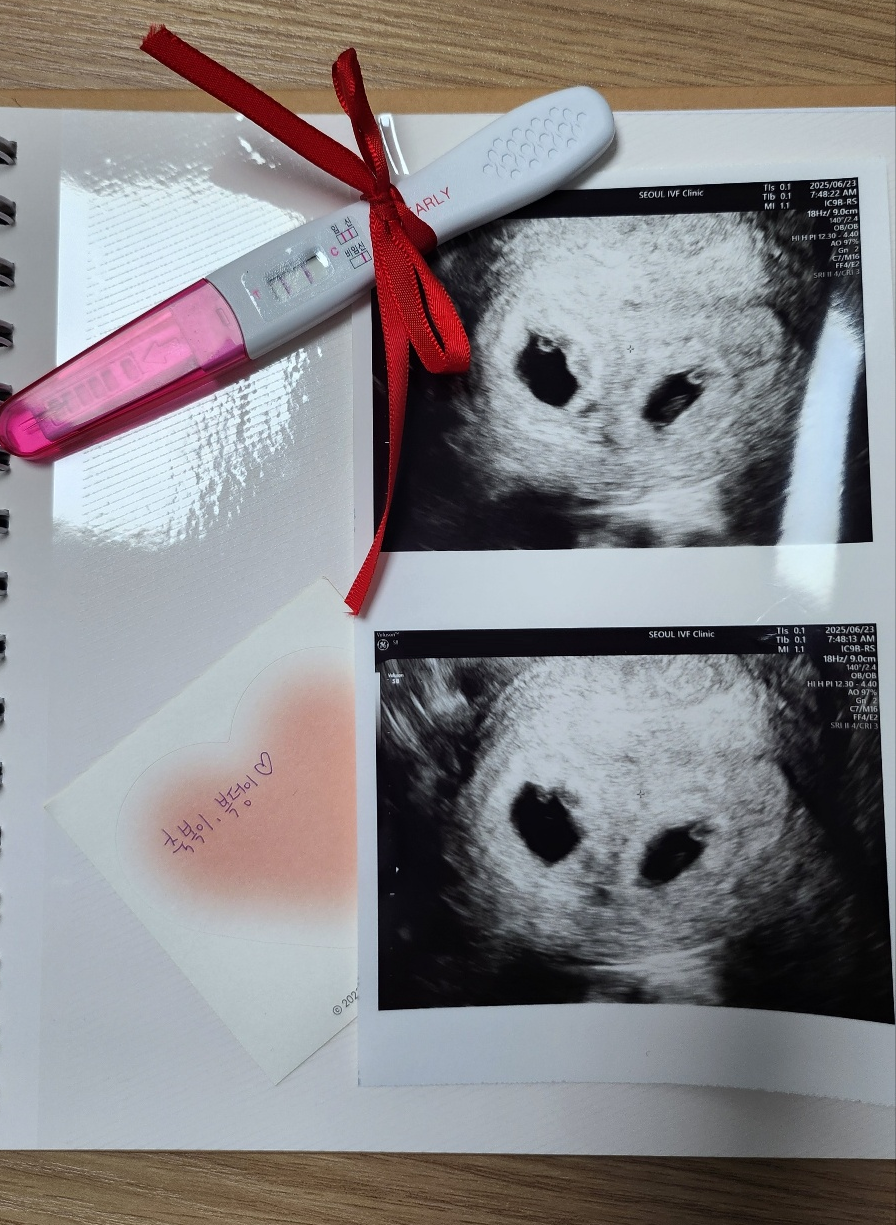

| 가슴 떨리는 임신 이야기를 공유해 주세요. | 인공수정에서 두 번 연속 실패하면서 크게 좌절했었습니다. 하지만 자궁내시경 후 바로 시험관으로 가자는 이유정 원장님 말씀을 듣고 용기를 내어 넘어가게 되었어요. 사실 첫 시도에서는 실패할 거라 생각해 큰 기대도 하지 않았습니다. 테스트기도 안해보고 병원에 갔어요. 그런데 1차, 2차 피검사 수치가 높게 나오고도 믿기지 않아 매일 테스트기를 붙잡고 살았던 기억이 납니다. 지금은 매일이 너무 행복하고, “더 일찍 병원에 올걸” 하는 생각을 자주 하게 됩니다. 이유정원장님께서 편안하게 해주시고 위로해주신 덕분에 1차때 바로 성공한것같아요 |

| 치료 도중 느꼈던 가장 기뻤던 순간과 절망적인 것들은 무엇인가요? 잊지 못할 경험이 있나요? | 매번 기대하고 병원에 갔다가 임신 수치가 아니었다는 소식을 들을 때마다 눈물이 나고 병원 오는 길이 무겁게 느껴졌습니다. 그만큼 인공수정 실패가 큰 절망이었습니다. 반대로 가장 설레고 기뻤던 순간은 이유정 원장님께서 제게 맞는 약을 처방해주셨을 때였습니다. 부작용도 없고, 걱정 없이 시술과 채취를 진행할 수 있다는 설명을 듣는 순간 처음으로 희망이 생겼습니다. 그리고 결국 시험관 1차 시도만에 성공하면서 그 벅찬 기쁨은 말로 다 표현할 수 없었습니다. |